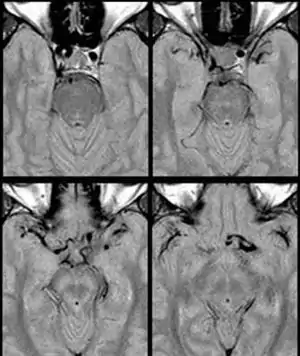

Internal carotid artery dolichoectasia is particularly interesting because the artery normally already contains one hairpin turn. Seen in an MRI as two individual arteries at this hairpin, a carotid artery dolichoectasia can progress so far as to produce a second hairpin turn and appear as three individual arteries on an MRI. In the case of a dolichoectasia of the Internal Carotid Artery (ICD), the pathogenesis is primarily related to compression of the optic nerves at the optic chiasma (see Fig. 1 and 2).